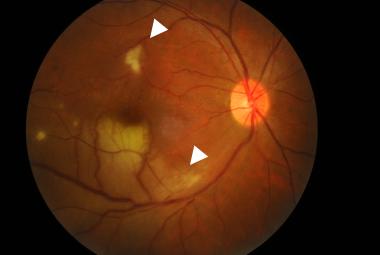

The current COVID-19 pandemic has prompted the development of vaccines to control the spread and severity of SARS-CoV-2. However, there are growing reports of different types of strokes, including ischemic and hemorrhagic strokes, as well as cerebral venous sinus thrombosis (CVST), following COVID-19 vaccination. We presented a case involving a 55-year-old male with a history of ischemic heart disease who exhibited an atypical presentation of visual field impairment one week following Sinovac-CoronaVac COVID-19 vaccination. The patient also experienced mild headache and vomiting for two days preceding the onset of visual symptoms. Right eye’s best-corrected visual acuity was 6/24, and left 6/15. A visual field confrontation test indicated left homonymous hemianopia. An urgent CT venography of the brain documented right transverse sinus thrombosis with occipital haemorrhagic infarct. A nasopharyngeal swab tested negative for SARS-CoV-2, and baseline blood investigations were within normal ranges. The patient was given one week of low-molecular-weight heparin, followed by a three-month course of oral anticoagulant. Post-treatment, there was marginal improvement, although a residual visual field defect persisted. In conclusion, while COVID-19 vaccination remains essential, clinicians must remain vigilant for rare adverse events like CVST and be prepared to manage these cases promptly to ensure patient safety.